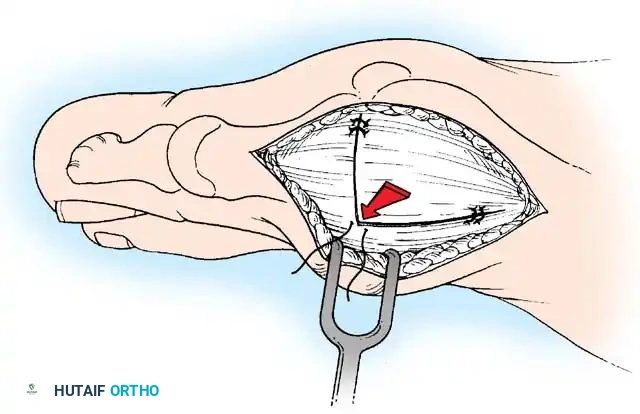

MEDIAL EMINENCE REMOVAL

• After inspecting the metatarsophalangeal joint for degenerative changes, loose bodies, or synovial abnormalities, remove the medial eminence by fi rst scoring with an osteotome its proximal edge where the eminence meets the shaft. Always consult the preoperative radiographs to determine how much of the medial eminence should be removed.

• Using the same osteotome or a power saw, begin the exostectomy distally at the parasagittal groove, and direct it medially toward the scored area on the metatarsal shaft (Fig. 7817). If a power saw is used, a 9-mm blade, rather than a 4to 5mm blade, is preferred. The medial direction of the osteotomy prevents splitting of the metatarsal shaft, especially if the proximal edge of the osteotomy has been scored as recommended.

• After the medial eminence has been removed, use a small rongeur to round off the dorsal and plantar edges of the medial aspect of the metatarsal head. Rasping the raw bone concludes the initial stage of the procedure. Use bone wax on the raw surfaces of bone of the metatarsal head.

ADDUCTOR TENDON AND LATERAL CAPSULAR RELEASE

• Begin the second stage with a dorsal longitudinal incision beginning 2 to 3 mm proximal to the dorsal aspect of the fi rst web space to avoid web contracture postoperatively; extend it proximally between the fi rst and second metatarsal heads for 3 to 4 cm (Fig. 78-18). This allows adequate exposure of the adductor insertion into the base of the proximal phalanx, the lateral head of the fl exor hallucis brevis muscle converging on the fi bular sesamoid, and the entire lateral capsule from the extensor hallucis longus muscle to the plantar plate.

• The main portion of the adductor tendon inserts into the base of the proximal phalanx just plantar to the longitudinal axis of the phalanx. It also has a smaller insertion, along with the lateral head of the fl exor hallucis brevis muscle, into the fi bular sesamoid. The simplest technique to identify the insertion of the adductor hallucis tendon is to place a small, pointed, curved hemostat on the dorsolateral base of the proximal phalanx, slide it fi rmly plantarward, and lift the hemostat dorsally and laterally; the tip of the instrument usually rests in the axilla of the insertion of the adductor tendon (Fig. 78-19A). This is comparable to securing the iliopsoas tendon for tenotomy at the lesser trochanter.

• When the primary insertion is released, grasp the tendon with forceps or a hemostat, and, with traction, displace it dorsally and laterally toward the second metatarsal so that further dissection is on the medial side of the adductor or push the sesamoid sling laterally through the previously placed medial incision to aid exposure.

• While spreading the fi rst and second metatarsal heads with a small Inge retractor, heavy-duty two-tooth retractors, or a Weitlaner retractor, hold the adductor tendon under tension, which facilitates exposure. The lateral head of the fl exor hallucis brevis muscle, the lateral border of the fi bular sesamoid, and the slip of the adductor tendon (confl uent with the lateral head of the fl exor hallucis brevis muscle) come into view in the depths of the wound.

• All attachments of the adductor into its conjoined insertion with the lateral head of the fl exor hallucis brevis muscle into the fi bular sesamoid must be severed; with traction on the adductor, it freely and independently moves without tethering the fi bular sesamoid (Fig. 78-19B).

• This deep transverse intermetatarsal ligament, which lies just plantar to the adductor, may be released by the incision along the lateral border of the sesamoid. If not, release this ligament, carefully preserving the neurovascular bundle immediately beneath it, and incise the lateral capsule. Mann emphasized that release of the deep transverse metatarsal ligament endangers the neurovascular bundle to the fi rst web space, which lies immediately beneath this ligament. Sliding a small Freer elevator between this ligament and the neurovascular bundle would protect the latter structures.